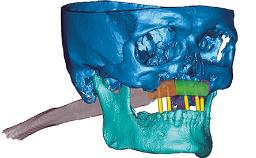

The author provides a step-by-step guide for meticulous planning and execution using a fully digital workflow. Of note, the maxillary rehabilitation was achieved in three phases using CAD/CAM technology: (1) PMMA provisional, fabricated prior to flapless guided implant placement and used to create the desired soft-tissue profile (2) PMMA definitive restoration prototype, used to confirm and perfect clinical details (3) Zirconia definitive restoration.